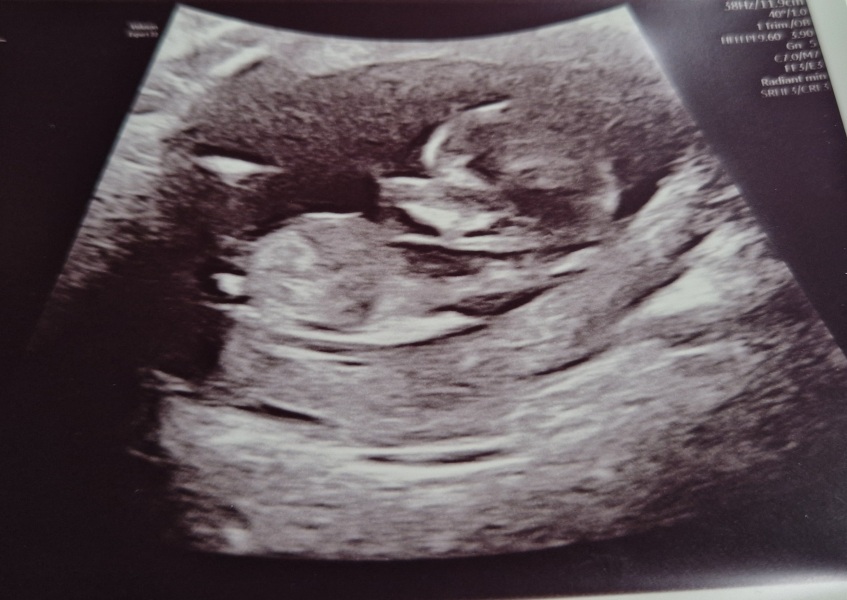

BadLobster · 14/03/2024 15:40

Had some bleeding over the past two days, so had a wee scan today to check everything was fine. Very relieved that all is good and we got a look at a very wriggly baby. Lots of kicking its little legs about and throwing its hands up. Very reassured after a pretty anxious couple of days.